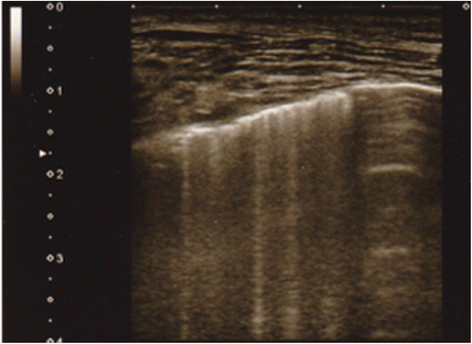

In recent years, the use of chest ultrasonography to detect lung water has received growing attention in clinical research focused on intensive care patients [8] and patients with heart failure [9]. The most commonly observed finding was a comet tail artifact fanning out from the lung-wall interface and spreading upwards to the edge of the screen, previously named a “B-line” (Fig. 1) [10]. In patients with heart failure, the number of B-lines was correlated with the degree of extravascular lung water [11], and a reduction in the number of B-lines reflected the efficacy of treatment [1]. Previous studies have also shown that lung ultrasound can detect extravascular lung water and can be used to show a significant reduction after a dialytic session (both hemodialysis and peritoneal dialysis) [12,13,14,15]. Existing data suggest that lung ultrasound characteristics might be suitable for assessing the ideal body weight in hemodialysis patients, since this technique is simple, inexpensive, nonionizing, and can easily be performed at the patient’s bedside [16, 17].

Lung ultrasound was performed at the first session of the week, the same time of peripheral blood sample preparation, using Vscan® (GE Healthcare, Japan), a hand-held ultrasound device with a wide-bandwidth phased-array probe (1.7–3.5 MHz) [20, 21]. Bilateral scanning of the anterior and lateral chest walls was performed with the patient in a supine position just after the start of the hemodialysis therapy. An intercostal scan with maximum extension of the visual pleural line was performed. The chest wall was divided into eight areas (two anterior and two lateral areas per side), and two scan was obtained for each area [22,23,24,25,26]. The anterior zone of the chest wall was designated from the sternum to the anterior axillary line and was then divided into upper and lower halves (from the clavicle to the third intercostal spaces and from the third space to the diaphragm). The lateral zone was positioned from the anterior axillary line to the posterior axillary line and was also divided into the upper and lower halves. Cardiologist, who is blind to the result of blood peripheral blood sample, attempted to detect comet tail artifacts fanning out from the lung-wall interface and spreading to the edge of the screen, which were previously named B-lines (Additional file 1: Movie S1) [23, 24]. The total number of B-lines was estimated. Echocardiographic measurements were obtained at the same time and left ventricular ejection fraction (LVEF) was estimated.

Additional file 1: Movie S1 B-lines detected by lung ultrasound using Vscan® (GE Healthcare, Japan). (mp4 2009 kb)